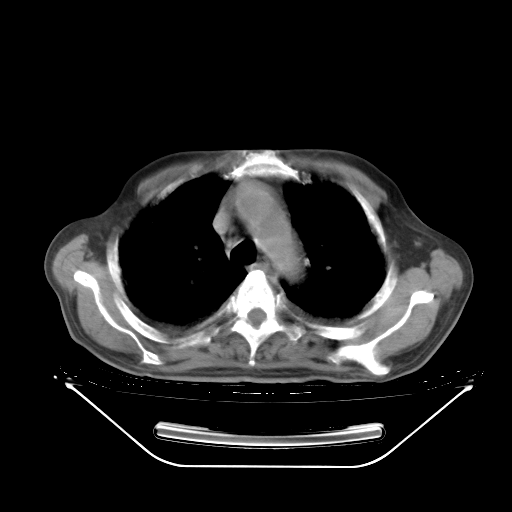

今天复查肺部CT,发现双肺广泛磨玻璃样改变。所以我把3月19日和5月9日相隔50天的肺部CT上传。请大家会诊。

5月9日肺部CT(在4月27日齐鲁医院肺部CT描述部分肺组织磨玻璃样改变,12天后肺组织广泛磨玻璃样改变)

2009年5月9日肺部CT

大致读了系列胸部CT:纵隔窗无明显异常,肺窗:从4、27至今:主要是双肺中下野外带可见毛玻璃样改变,目前处于急性肺泡炎阶段,至于原因考虑1、结替组织或胶原血管性疾病所致?2、恶性疾病如恶组在肺部所致的表现或细支气管肺泡癌?3、药物或其它原因如肺蛋白沉着症所致肺泡炎目前不太可能?总之,明天就去请我院的呼吸科、感染科、血液科和临免专家会诊哈。